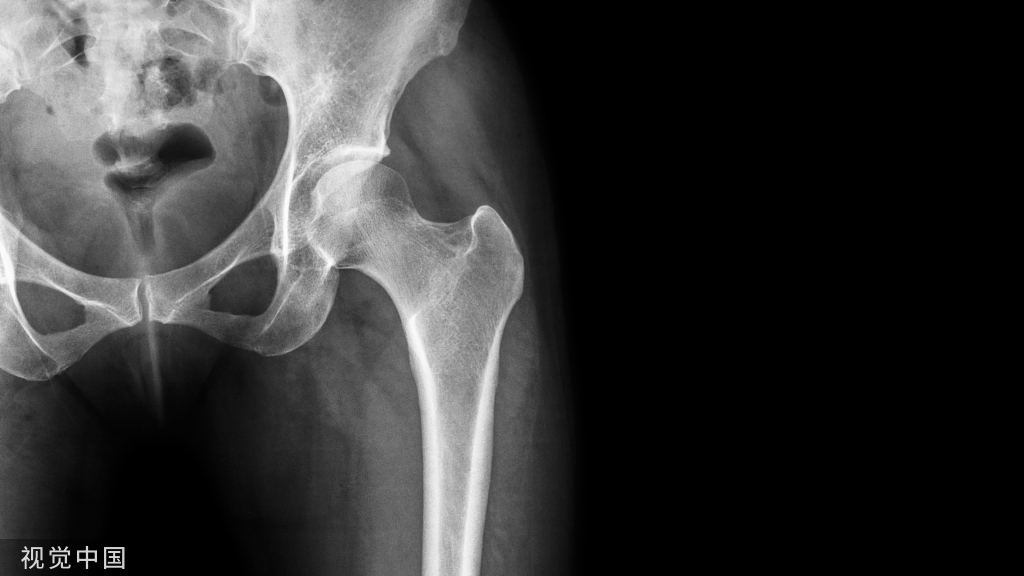

弹响低钝且频仍,响声发自骨外侧的髌股关节,同时伴关节肿胀,偶有交锁征象。MRI可看到关节退变,半月板呈“孤岛样”。关节镜下可看到关节软骨及半月板退变、骨质增生压迫韧带和关节囊。

平常见于支撑带挛缩、髁浅平、高/低位髌骨者。膝前弹响,声音清脆或低钝,频率高,伴有摩擦感或捻发音,髌骨勾当度差,髌周有压痛,研磨及阴抗试验都呈阳性。轴位片可以表示髌股关节适配差,正位片可以看到高/低位髌骨。关节镜可看到髌骨外倾或半脱位较多见,髌股关节面有软骨退变。

病因尚不了然,多继发于膝关节外伤,临床少见。弹响低钝,髌上囊或髁间窝可摸到质地坚硬的肿物,可能伴有关节交锁和屈伸受限。若是钙化严峻X光可以看到,MRI可以确诊。关节镜下可以看到滑膜增生、钙化,嵌顿于关节间隙,摩擦或撞击软骨。

病因不明,外伤时可诱发。弹响低钝,位置不确定,频率低,膝关节压痛弥散,伴关节肿胀,交锁少见。MRI可看到滑膜增生,呈结节状。关节镜下可看到滑膜充血增生,含铁血黄素沉积,侵蚀关节软骨和韧带。

外伤引起。膝关节不稳导致弹响,频率低且低钝,可伴有交锁,抽屉试验阳性。核磁可明晰诊断。关节镜下可看到韧带断端嵌于关节间隙,或有软骨损伤。